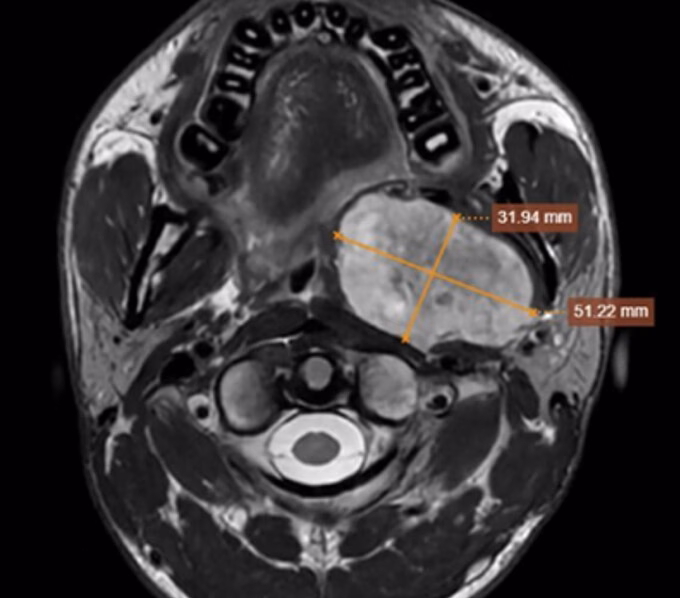

Tình trạng của Hoàng chỉ trở nên nghiêm trọng trong hai tuần gần đây khi vùng góc hàm trái của anh bắt đầu sưng và xuất hiện một khối cứng. Khối này không di động và không gây đau, nhưng sự xuất hiện của nó đã khiến Hoàng tìm kiếm sự giúp đỡ y tế. Khi đến bệnh viện, các bác sĩ đã tiến hành thăm khám và thực hiện các xét nghiệm cần thiết để xác định nguyên nhân của khối u và triệu chứng nghẹn mà Hoàng đã trải qua.